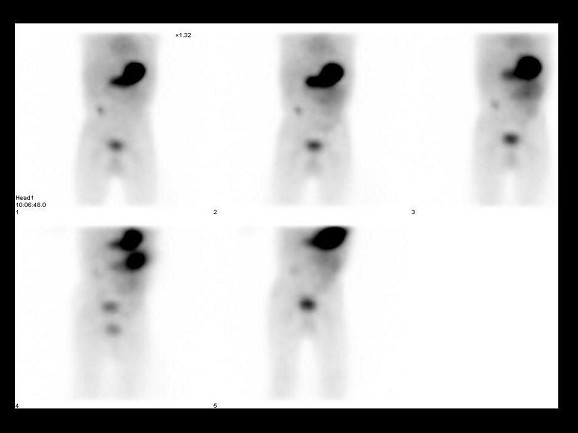

[多选题]2岁男孩,下消化道出血4天,行TcO腹部显像如图,可能的诊断是()A.异位胃粘膜B.Meckel憩室C.Barret食管D.肠重复畸形E.未见异位胃粘

[单选题]17岁男孩,突发黑便3天,行TcO腹部显像如图,正确的诊断是()A.箭头所示异位胃粘膜B.箭头所示Barrett食管C.箭头所示肠重复畸形D.箭头所示